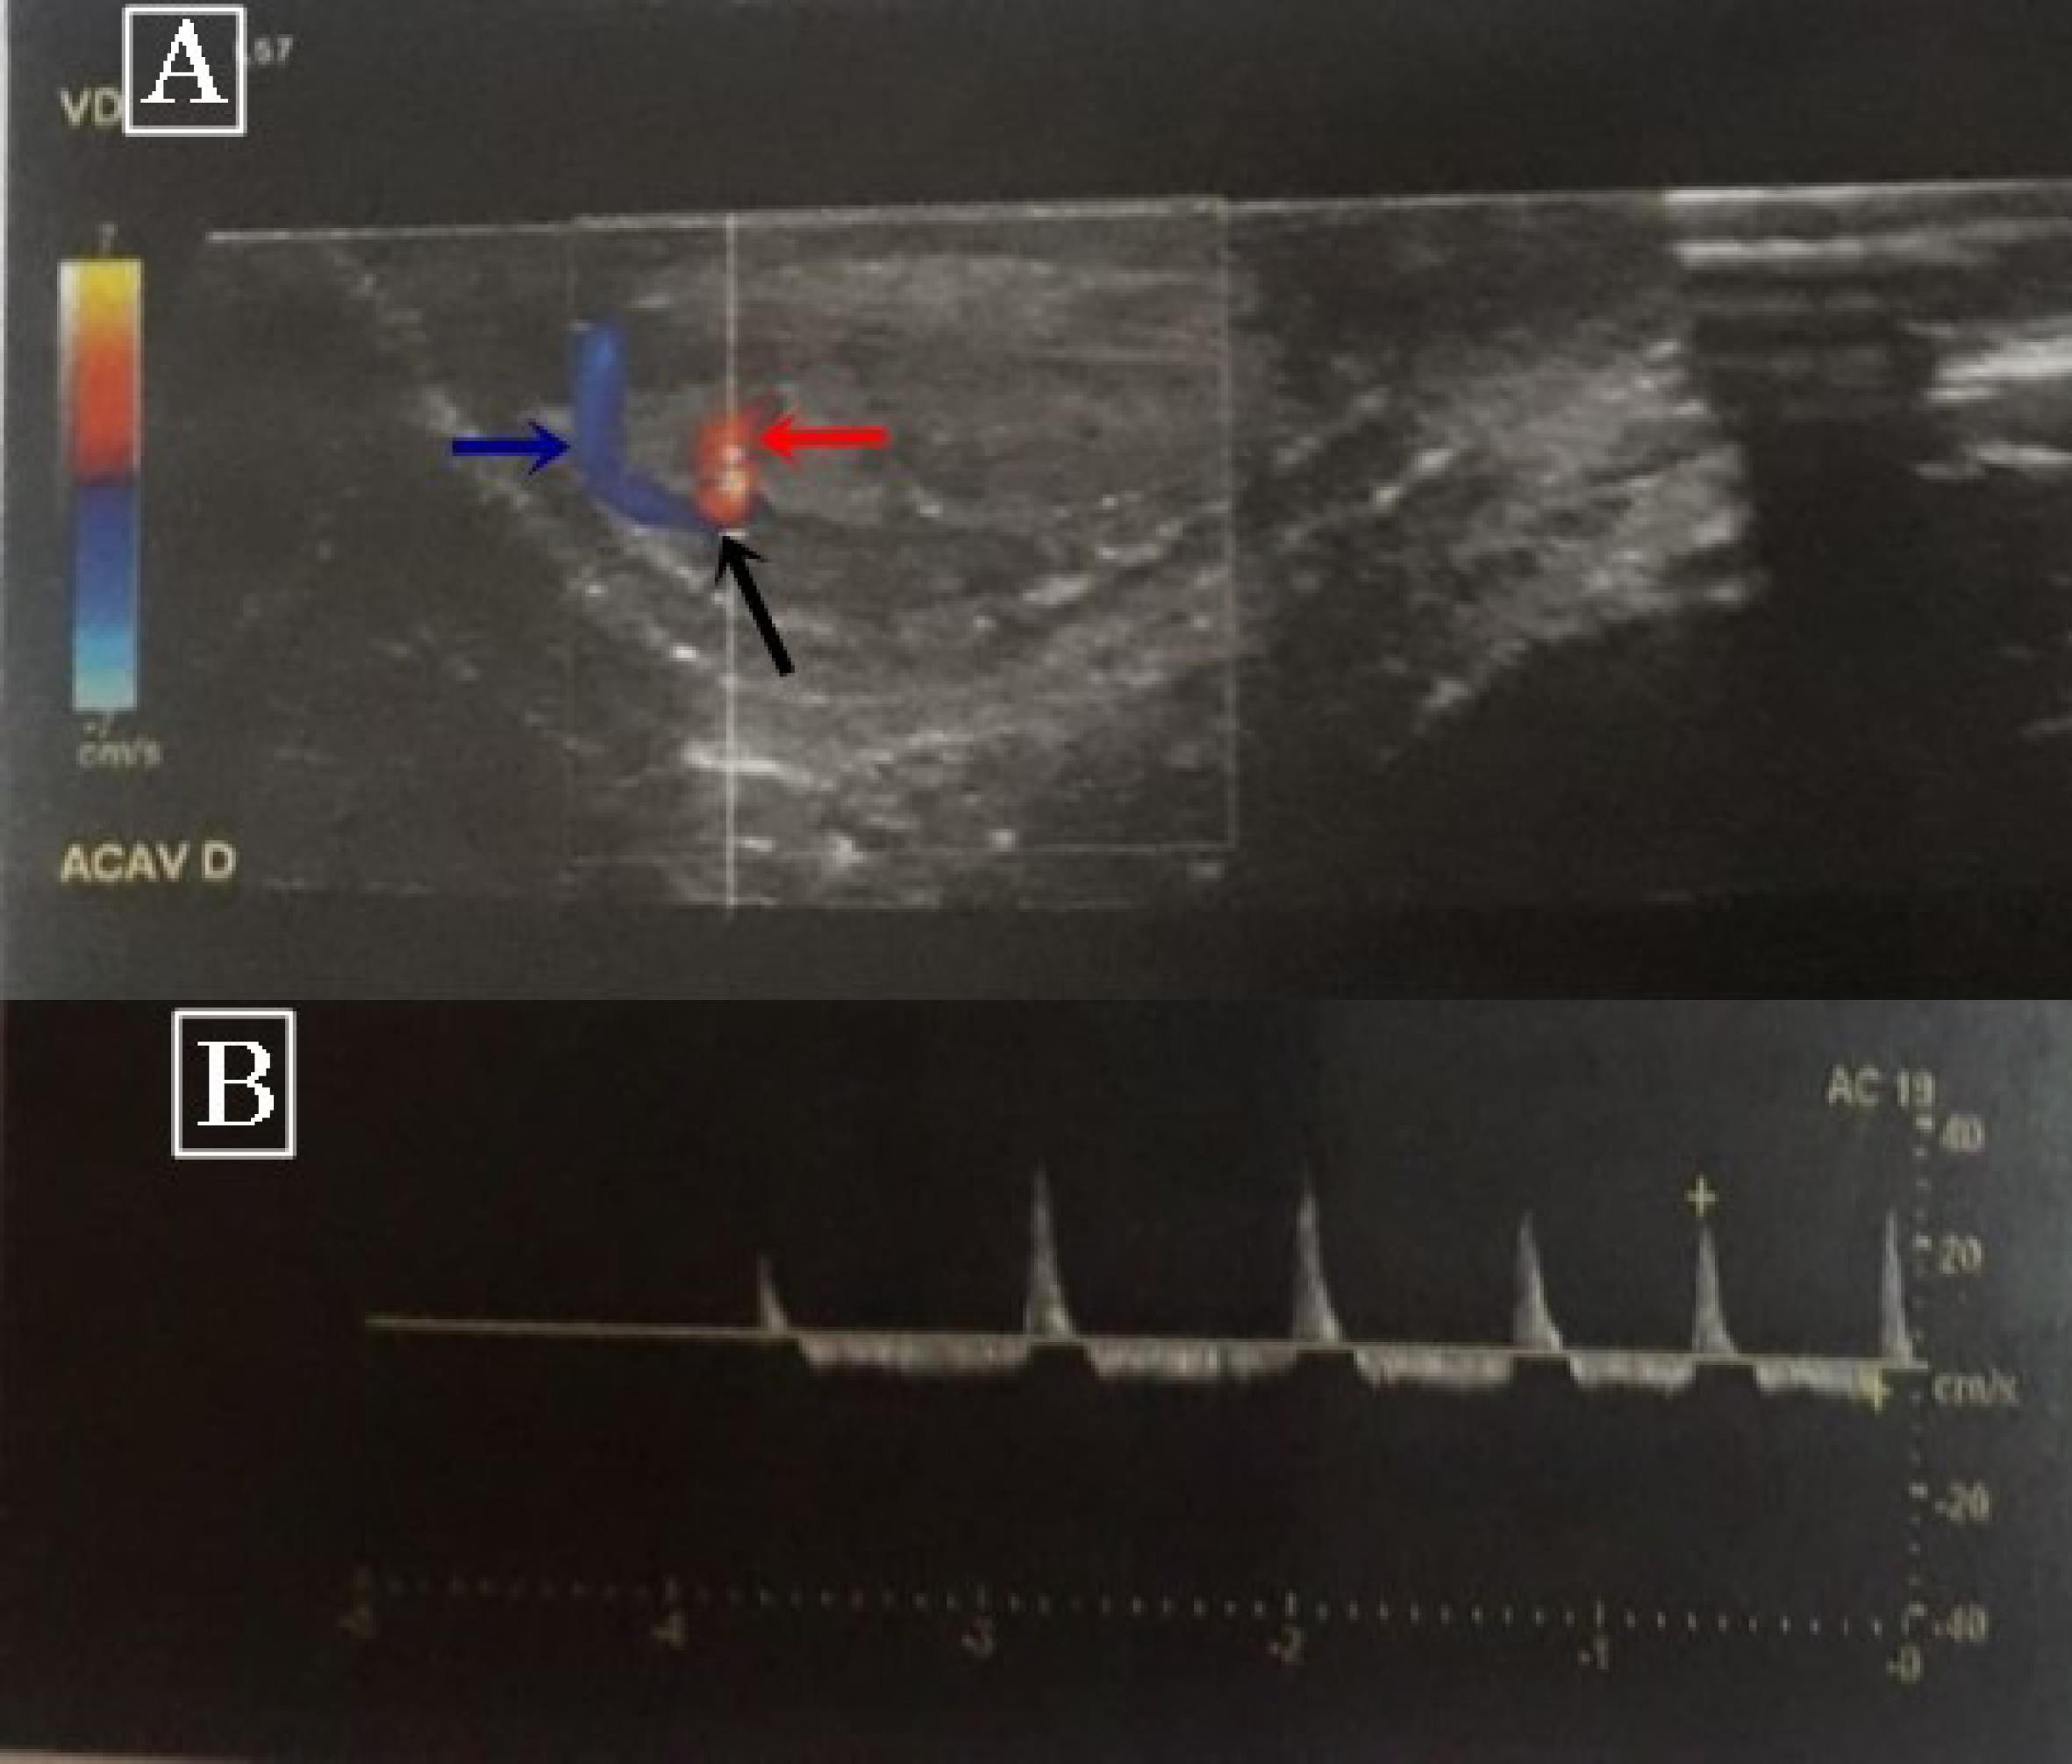

Physical examination showed an erect, normally circumcised, non-tender penis. The corpora cavernosa was rigid and the glans was soft. The laboratory work-up, including a complete blood count and a cytobacteriological examination of the urine, was normal. Penile color Doppler ultrasound revealed an arteriolar-sinusoidal fistula at the base of the left corpus cavernosum with a high flow rate of 34 mL/s at the level of the fistula (Figure 1). Based on these findings, we opted for a conservative treatment consisting of analgesics with clinical observation. Two days after hospital admission, the priapism resolved spontaneously. The child has been followed as an outpatient for 3 years, and has not experienced any recurrence to the present time.

Color Doppler Ultrasonography. (A) Red, blue and black arrows show arterial blood flow, venous blood flow, and arteriolar-sinusoidal fistula, respectively. (B) High blood flow rate at the level of the fistula

Patients with high-flow priapism usually present with non-tender, partially tumescent corpora cavernosa. In such cases, Doppler ultrasound examination of the penis is the gold standard for the diagnosis. It can assess intracorporeal arterial blood flow in real time. In patients with non-ischemic priapism, Doppler ultrasonography of the penis shows normal or increased velocity of blood flow in the corporal arteries.8 It can also reveal an arteriolosinusoidal fistula, as in our patient’s case.